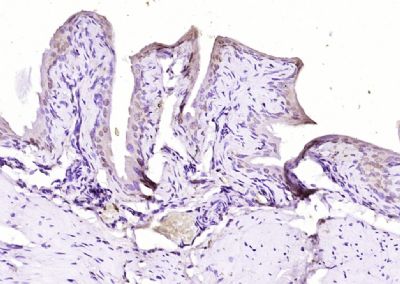

面肩肱型肌营养不良症相关蛋白FRG1抗体

目录号:bs-13215R

商品规格:100ul